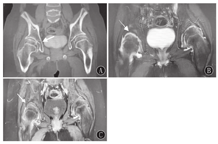

X线及CT检查:14例患儿影像学检查均存在异常,各部位X线检查均可见骨密度降低。长骨及手:干骺端明显膨大,其中以食指、中指掌指关节及近端指间关节远端受累显著(图3)。掌骨、指骨干骺端膨大14例、腕关节干骺端膨大7例、膝关节干骺端膨大8例;关节间隙狭窄6例,骨骺提前闭合及骨龄提前7例。骨盆平片表现为双髋关节间隙狭窄11例,股骨头骨骺扁平8例(图4A),股骨颈变短2例、股骨头外移4例,关节面硬化、囊变、骨质破坏8例。脊柱:椎体普遍变扁,上下缘形态不规则、前上下缘可见骨质缺损,椎间隙变窄、中后部明显,椎弓根变短(图5);颈椎受累1例,胸、腰椎受累13例。

磁共振成像:髋关节磁共振成像检查表现除X线片中所见的关节间隙狭窄、关节面硬化、囊变、股骨头骨骺扁平外,还可见关节腔积液,增强扫描可见滑膜增厚、强化,以及关节面下骨髓水肿改变(图4B、图4C)。